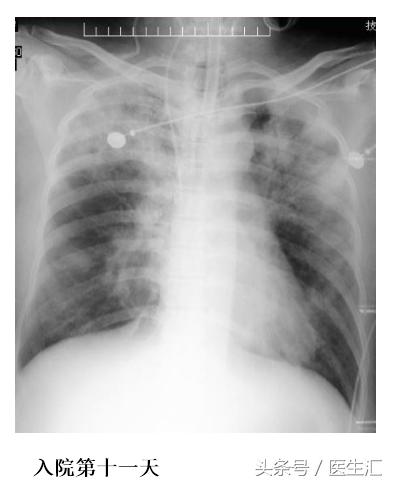

血常规:白细胞 28.49×10^9/L、红细胞 4.47×10^12/L、血红蛋白141.00g/L、血小板150.00×10^9/L,胆碱酯酶<200U/L,生化钾 3.27mmol/L、淀粉酶 315U/L、钠135.5mmol/L、氯 108.2mmol/L、肌酐 56.2μmol/L,脑利钠肽前体858.100pg/ml,凝血常规、凝血酶原时间 15.8s、活化部分凝血活酶时间47.5 s,D-二聚体 1185ug/L。胸片:拟右下肺野少许渗出灶。